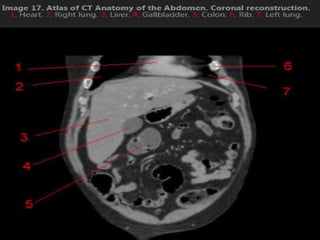

CT cross sectional anatomy.

CT – computedtomography. •Cross-sectional modality with capabilities for multiplanar reconstruction and dynamic imaging to assess vascularity •Tube rotates around the body and a circle of stationary detectors detects the penetrating x-rays forming an image.